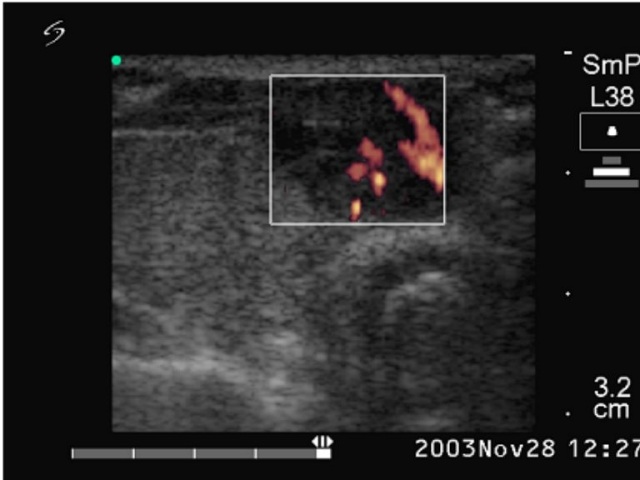

Ultrasonography: echonormal thyroids with two nodules close to each other in the isthmus. They were hypoechogenic inhomogeneous and exhibited irregularly increased intranodular blood flow.